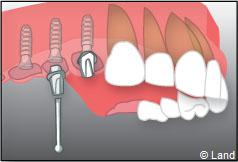

Exemple d’un implant unitaire pour remplacer une dent antérieure manquante.

Exemple de 3 dents manquantes remplacées par 3 couronnes sur implants.

Pose des piliers prothétiques et des 3 couronnes scellées.